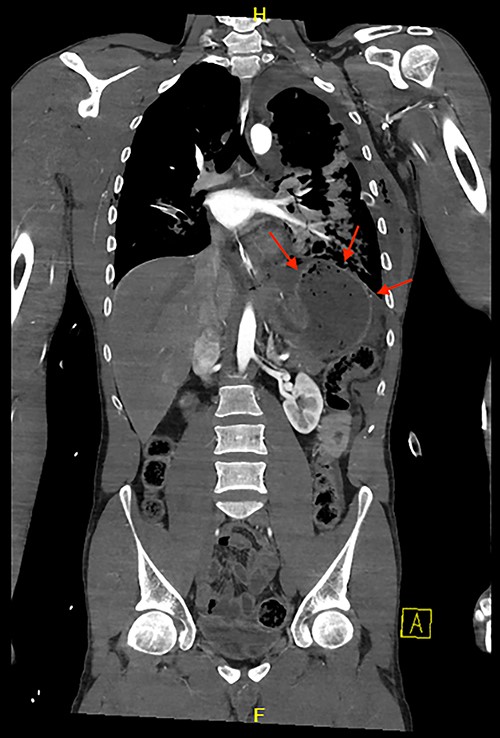

CT scan revealed a large left haemothorax and evidence of left diaphragmatic rupture with herniation of abdominal organs to thoracic cavity such as the spleen, stomach and splenic flexure of the colon; fractured all 12 left ribs, pulmonary contusion, unstable fractures of T6, T10 with acute spinal cord injury (complete transection; Figs 1–3).

Coronal view of CT chest and abdomen with herniation of the stomach and spleen into the thoracic cavity.